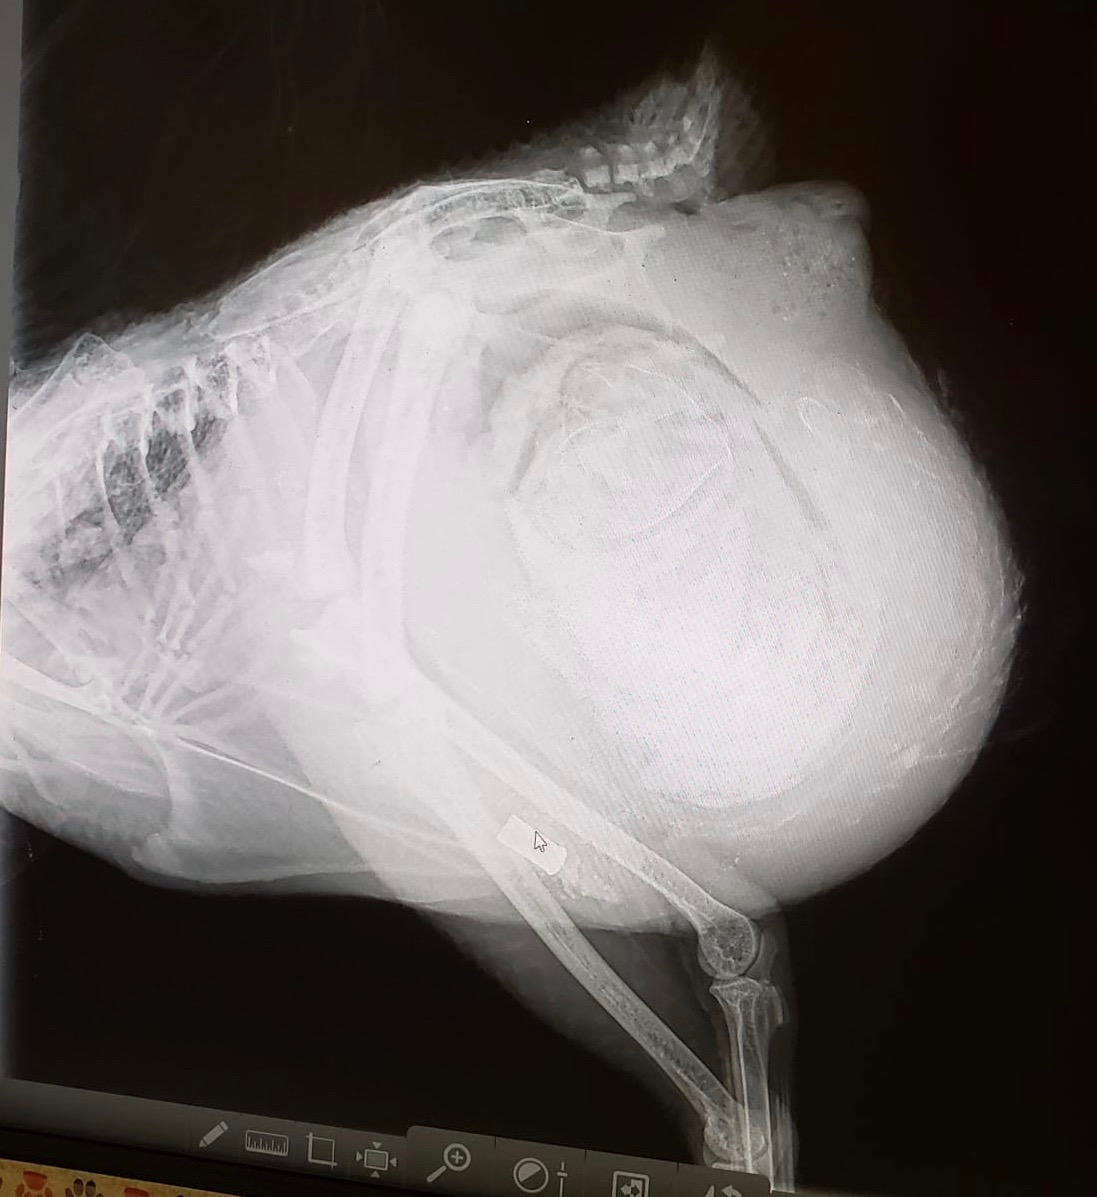

Day 2: I’m a Vet Tech/Assistant and took her to the all species Vet at my clinic for X-rays, which revealed a large mass in her abdomen. The doctor and I knew the mass was calcified from looking at the radiographs (tissue masses do not show up as bright on X-rays). I felt like a horrible chicken mum for having missed it.

Later that day Pretty Girl was prepped for surgery. I monitored the anesthesia while the Vet made a 5” incision and removed a whopping 2.1 lbs of accumulated material from internally laid eggs. Some of the egg yolk material had leaked in between her abdominal muscles. The area was flushed with a litre of NACL (sodium chloride), which is the least caustic chemical to use on tissue in the abdominal cavity.